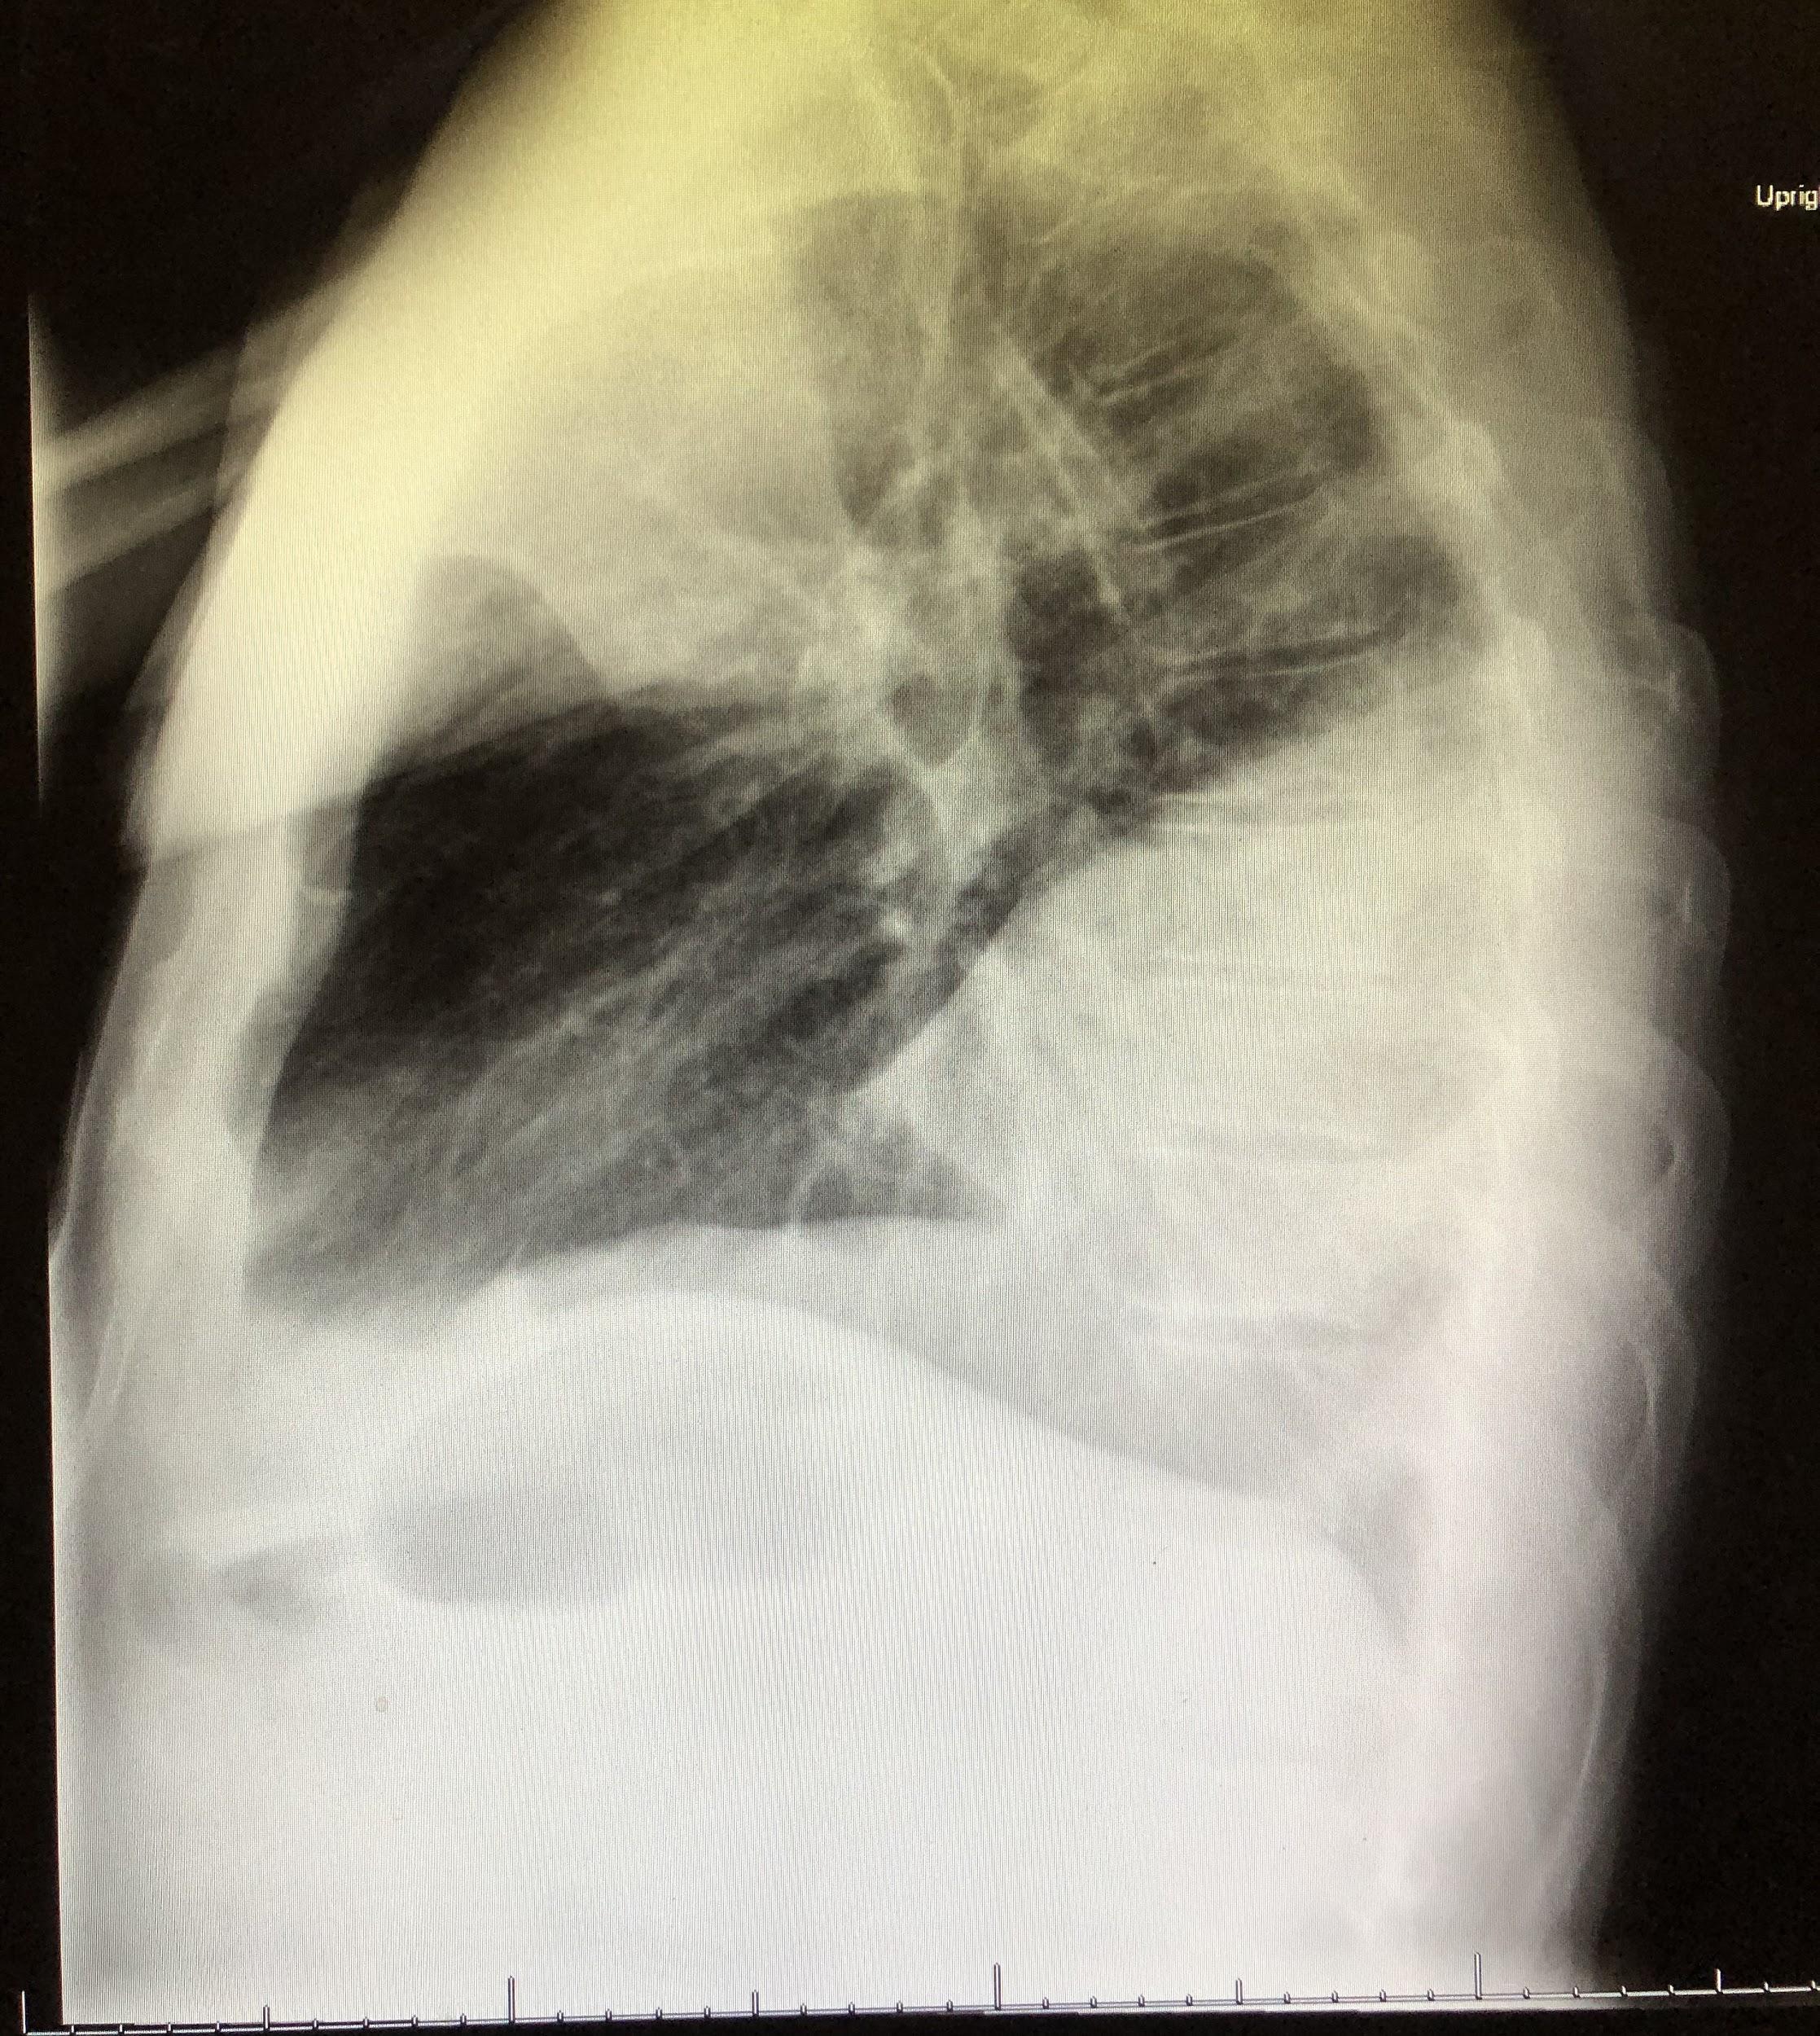

Chest radiographs revealed a dense consolidation in the right lower lobe (Figure 1). Additional imaging included right upper-quadrant ultrasonography, the findings of which were notable for mild intrahepatic dilation and mild biliary sludging. An empiric antibiotic regimen was initiated for community-acquired pneumonia with ceftriaxone, azithromycin, and doxycycline; this regimen subsequently was modified to vancomycin, azithromycin, and cefepime.

Figure 1. Anteroposterior (top) and lateral (bottom) chest radiographs showed an area of focal consolidation in the right middle and lower lung.